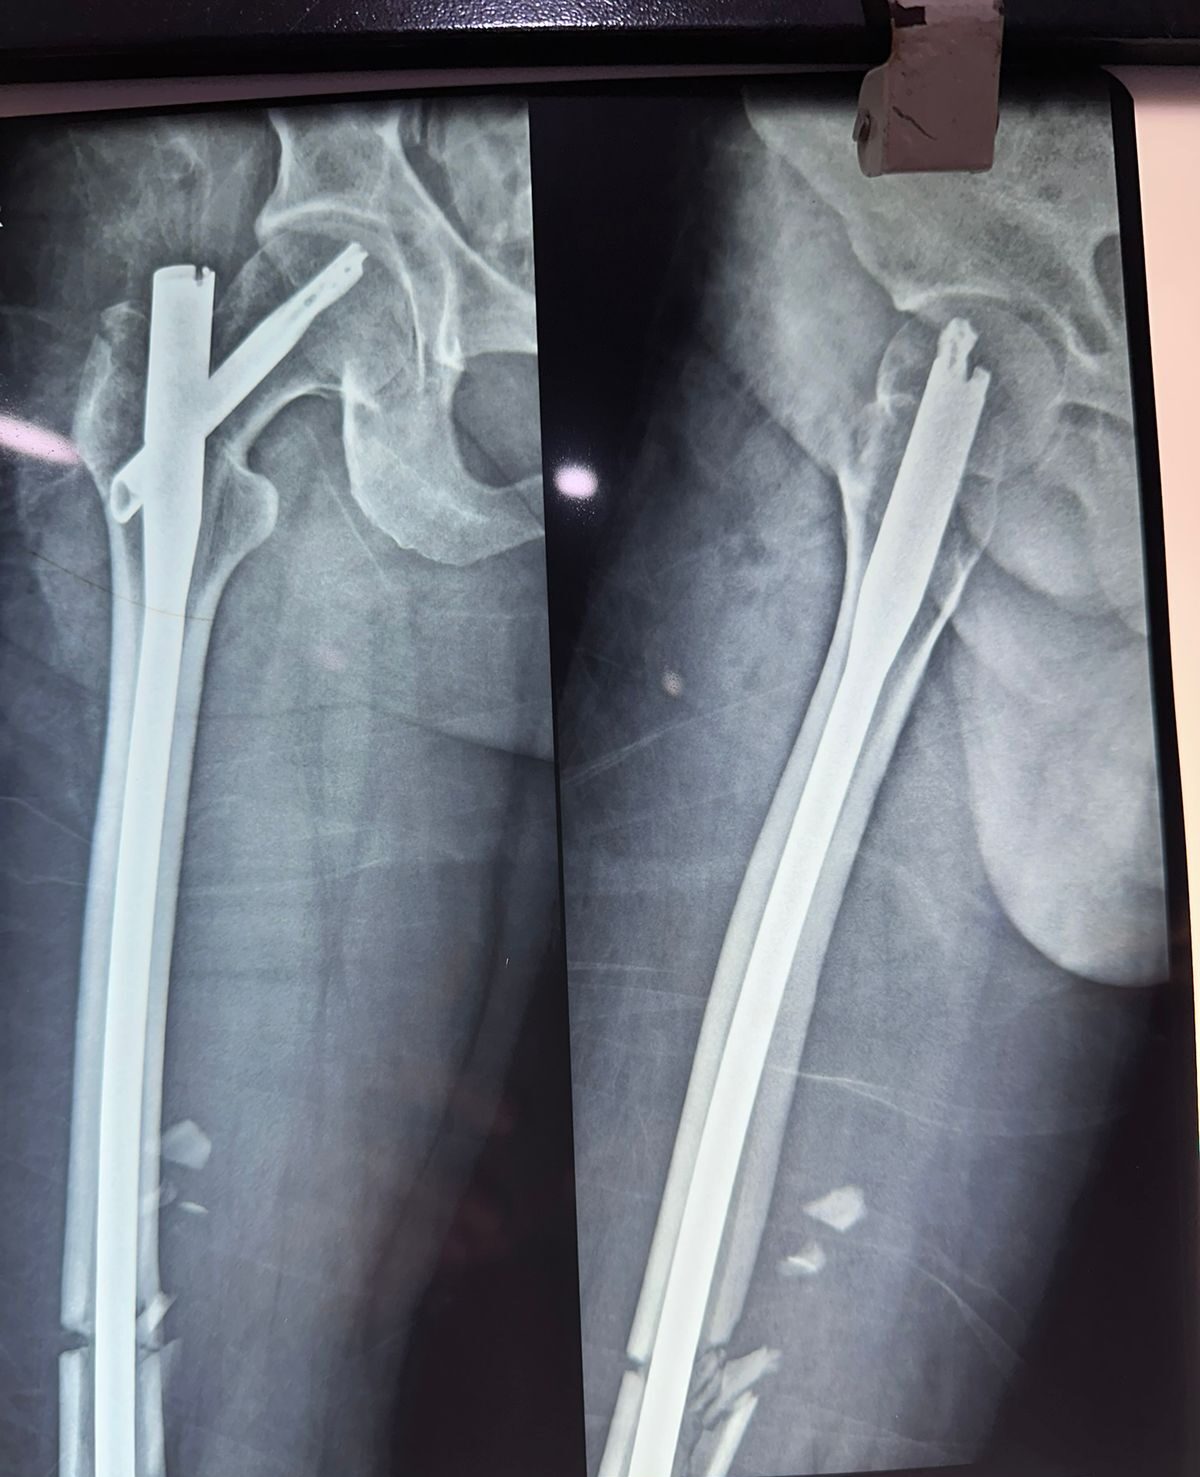

Moments That Mark Meaningful Recovery

Witness real patient transformations at The Ortho Clinic through images that reflect successful treatments and restored mobility.